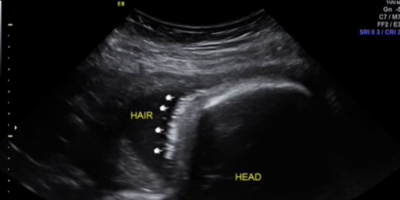

Sve detalje napretka trudnoće, odlazak na preglede kao i sam porođaj, roditelji su podelili sa ljudima koji ih prate na društvenim mrežama. Oni su prošle godine išli na ultrazvuk kako bi pratili napredak devojčice. Pregled je bio zakazan 26. septembra 2023. godine. Tada su na ultrazvuku videli svoju devojčicu, ali i nešto drugo što im je privuklo pažnju.

Sliku sa ultrazvuka prikazali su i u videu na TikToku. Naime, devojčica je imala kosu koja je jasno bila obeležena strelicama. Nakon ovog videa, slede slike sa porođaja. Tek tada, kosa je zaista bila primetna i mnogi su bili oduševljeni kako je lepa, gusta i crna.

- Ova devojčica je zapravo rođena sa baš malo kose - napisala je ironično majka devojčice u opisu videa na TikToku.

"Bila sam šokirana kada sam videla dlake na ultrazvuku, nisam znala da je to moguće", "Sigurno si umirala od mučnine", "U kojoj nedelji na ultrazvuku si videla da ima kosu", "Kako je ovo moguće?", "Moja beba je imala kosu, a ja nisam imala mučnine", "Preslatka mala devojčica", pisali su joj oduševljeni ljudi ispod videa javno.